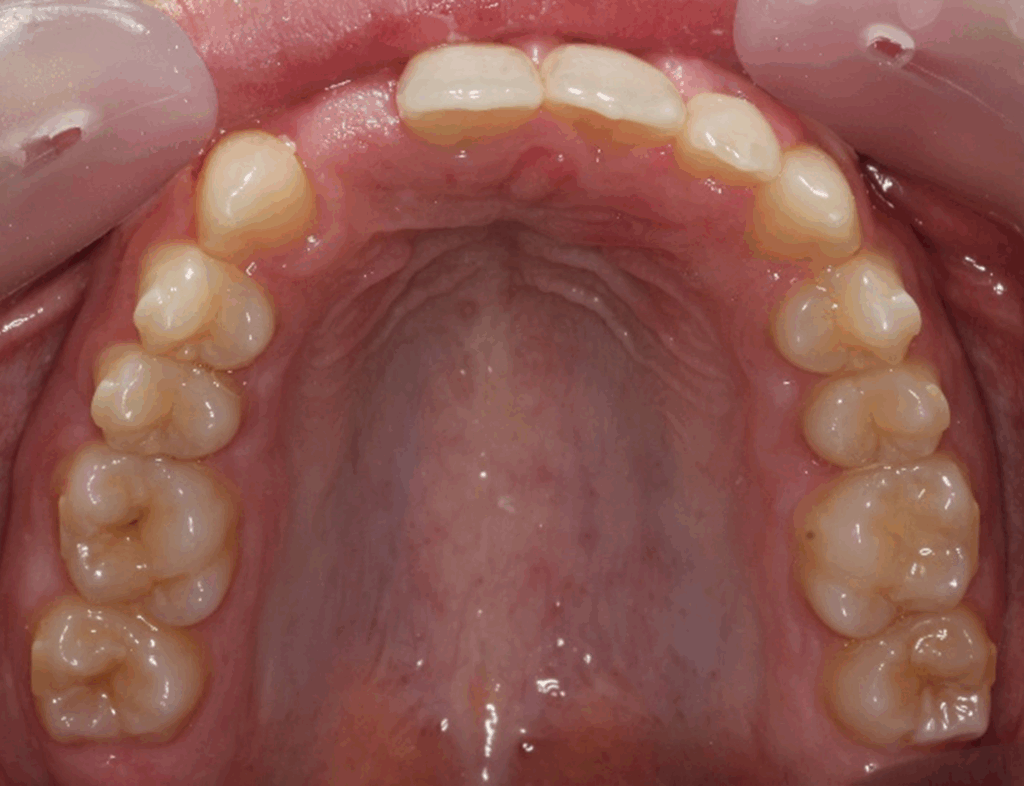

Two finishing stages were carried out after CBCT

18 aligners then 9 aligners (TruGen XR™)

This case demonstrates the accuracy and efficiency of Spark Aligners in:

Spark provided predictable movements, excellent aligner fit, and precise finishing, enabling successful orthodontic outcomes and future prosthetic.